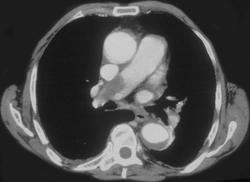

Bronchiectasis